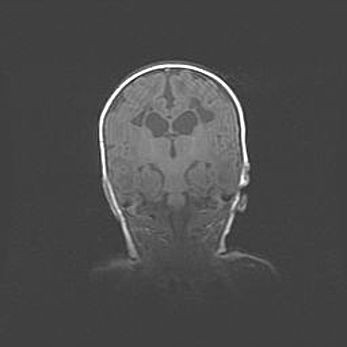

Открытая гидроцефалия.

Возраст: 9 месяцев 12 дней

Вес: 6800 г

Пол: мужской

Окружность головы: 41,5 см

Срок гестации: 28 недель

Гидроцефалия головного мозга у новорожденных имеет характерный признак: опережающий рост окружности головы приводит к визуально хорошо определяемой гидроцефальной форме сильно увеличенного в объёме черепа. Детские неврологи определяют следующие симптомы гидроцефалии у грудничков: выбухающий напряжённый родничок, частое запрокидывание головы, смещение глазных яблок к низу.